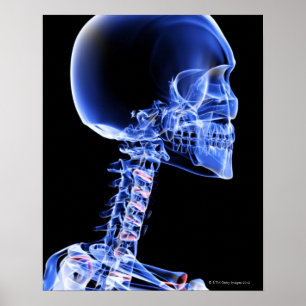

Bones of the Head and Neck Poster

Price$40.80